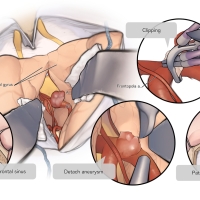

術後イラストシリーズ

OPExPARKコンテンツ・脳神経外科速報寄稿シリーズ